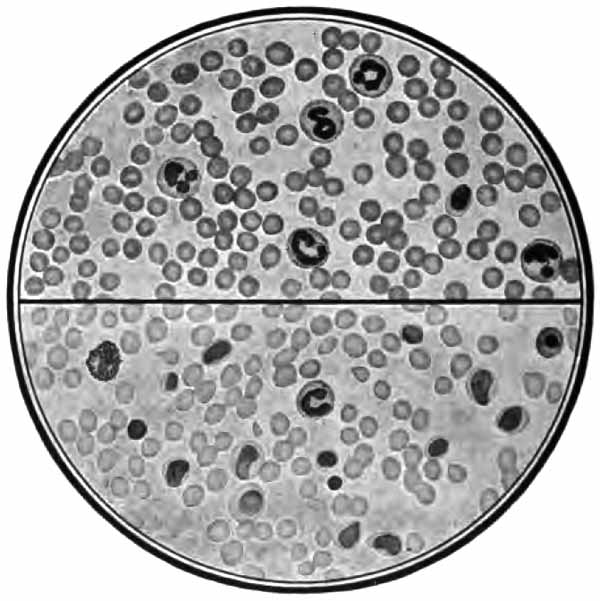

In films stained by Gabbet's method tubercle bacilli, if present, will be seen as slender red rods upon a blue background of mucus and cells (Plate II, Fig. 2). They average 3 to 4 µ in length—about one-half the diameter of a red blood-corpuscle. Beginners must be warned against mistaking the edges of cells, or particles which have retained the red stain, for bacilli. The appearance of the bacilli is almost always typical, and if there seems room for doubt, the structure in question is probably not a tubercle bacillus. They may lie singly or in groups. They are very frequently bent and often have a beaded appearance. It is possible that the larger, beaded bacilli indicate a less active tuberculous process than do the smaller, uniformly stained ones. Sometimes they are present in great numbers—thousands in a field of the one-twelfth objective. Sometimes several cover-glasses must be examined to find a single bacillus. At times they are so few that none are found in stained smears, and special methods are required to detect them. The number may bear some relation to the severity of the disease, but this relation is by no means constant. The mucoid sputum from an incipient case sometimes contains great numbers, while sputum from large tuberculous cavities at times contains very few. Failure to find them is not conclusive, though their absence is much more significant when the sputum is purulent than when it is mucoid.

PLATE II

Heart-failure cells in sputum

FIG. 1.—Heart-failure cells in sputum, containing blood-pigment, from a case of cardiac congestion of the lungs (Jakob).

Sputum showing tubercle bacilli

FIG. 2.—A, Sputum showing tubercle bacilli stained with carbol-fuchsin and Gabbet's methylene-blue solution (obj. one-twelfth oil-immersion); B, sputum of anthracosis, showing particles of coal-dust stained with methylene-blue (obj. one-twelfth oil-immersion) (Boston).

(2) Staphylococcus and Streptococcus (p. 262).—One or both of these organisms is commonly present in company with the tubercle bacillus in the sputum of advanced phthisis (Plate II, Fig. 2). They are often found in bronchitis, catarrhal pneumonia, and many other conditions.

(1) Pus-corpuscles are present in every sputum, and at times the sputum may consist of little else. They are the polymorphonuclear leukocytes of the blood, and appear as rounded cells with several nuclei or one very irregular nucleus (Fig. 8 and Plate II, Fig. 2). They are frequently filled with granules of coal-dust and are often much degenerated. Such coal-dust-laden leukocytes are especially abundant in anthracosis, where angular black particles, both intra- and extra-cellular, are often so numerous as to color the sputum (Plate II, Fig. 2, B). Occasionally mononuclear leukocytes are present.